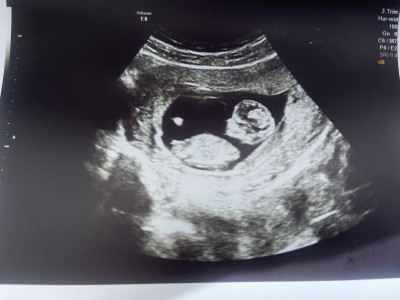

Resimli bakın size zahmet 🙏

Gebelik haftası 11+5

Yüzde yüz kız 😁🥰

Kesinlikle nub yani genital çıkıntı 30 dereceden küçük ve net belli kesinlikle yüzde yüz kız

Kız çocuk bence sağlıkla gelsin canım nub u yukarda değil

Kız canım aynı hafta aynı fotoğraf bendr de var şuan 20 haftalık ve kız 3 farklı doktor bana kız dedi doktordan önce kendim de görmüştüm aynısı sendr de var hayırlı olsun